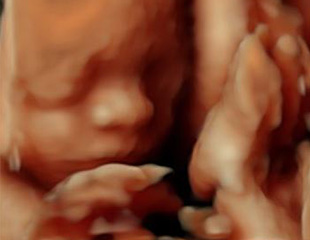

4Dエコー検査を行っています

当クリニックでは最新の超音波装置を用いた妊婦健診をおこなっています。お腹の中で元気に成長している赤ちゃんの表情や様子をリアルタイムの動画で見ることができます。かわいい赤ちゃんのしぐさがみられますよ。

市販のUSBメモリーをお持ち頂ければ、検査の一部分を記録させて頂きます。健診に一緒に来ることができない家族の方にも、ご自宅のパソコンで赤ちゃんの様子を見てもらうことができます。